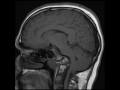

Basilar Impression

53-year-old female with a history of chronic neck pain and headaches. There is upward displacement of the anterior arch of the atlas and dens into an otherwise normal appearing foramen magnum. There is effacement and crowding of the foramen magnum with prominent kinking of the cervicomedullary junction. In this patient without underlying osseous abnormality, this is a case of basilar impression. Basilar impression may be either congenital or acquired. There is upward displacement of vertebral elements into a normal foramen magnum. The upward migration results in stenosis of the foramen magnum with compression of the medulla. Syringomyelia may be seen.